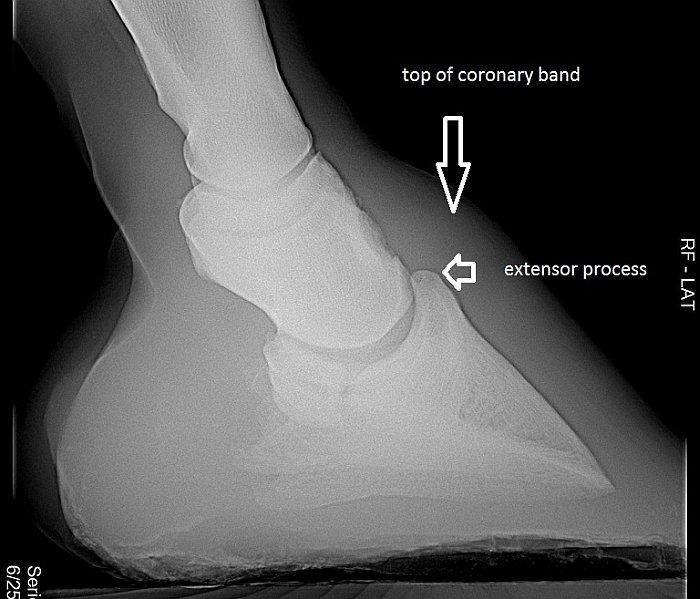

Pokud je výška kopytních kostí konstantní, můžeme vyvodit, že příliš dlouhá a/nebo příliš vysoká kopytní pouzdra nemohou být známkou zdravých kopyt, a my si můžeme na tento fakt dost rychle "natrénovat oči". Je však stále ještě rozdíl v tom, jak vysoko se kopytní kost v kopytním pouzdře nachází. Obvykle úplný vrcholek kopytní kosti, natahovačový výběžek, se nachází asi 6-8 mm pod vrcholkem korunky. U divokých koní je dokonce ještě výš, což jim umožňuje mít kratší kopytní pouzdra. U nemocných kopyt je často umístěna níž, tento stav se nazývá „nadměrně distální uložení" kopytní kosti. (Pete Ramey o tom napsal výborný článek http://www.hoofrehab.com/jessica.htm).

Obrázek 6 je rentgenový snímek kopyta. Vypadá to, že kopytní kost na něm je uvnitř pouzdra správně vysoko, přestože na tomto snímku není dostatečně zřetelně zviditelněná korunka. Mnoho veterinářů to nedělá.